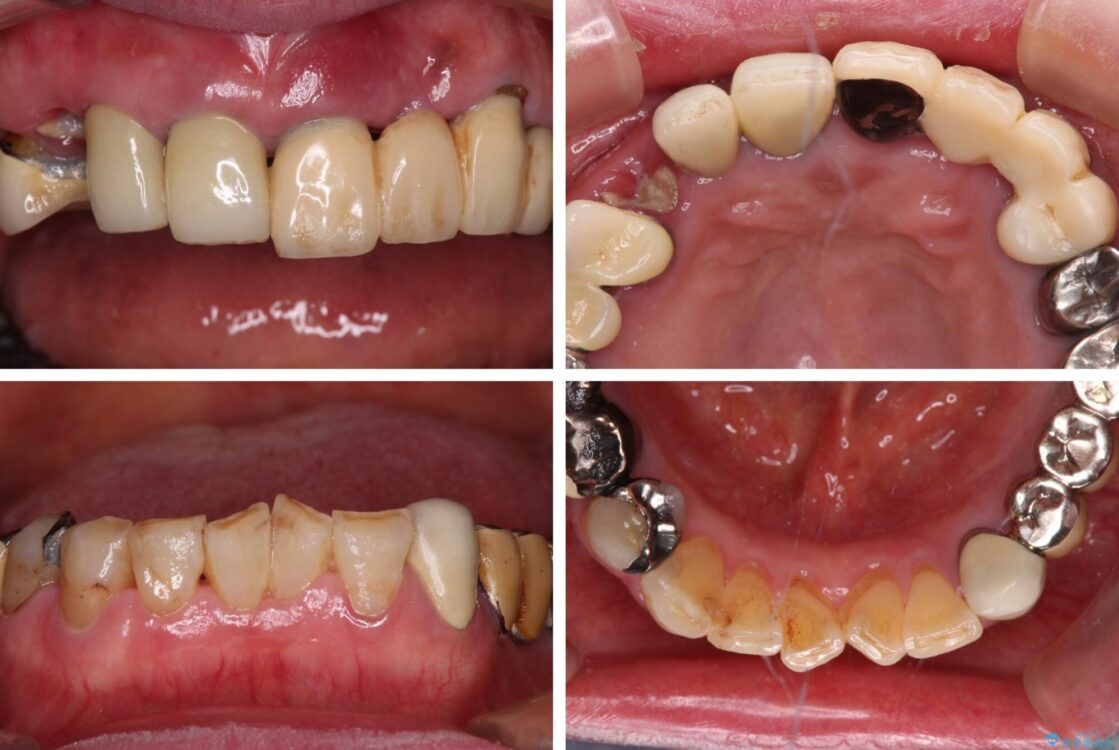

治療前

• 前歯をきれいにしたい インプラントや部分矯正を用いた総合歯科治療 治療前画像